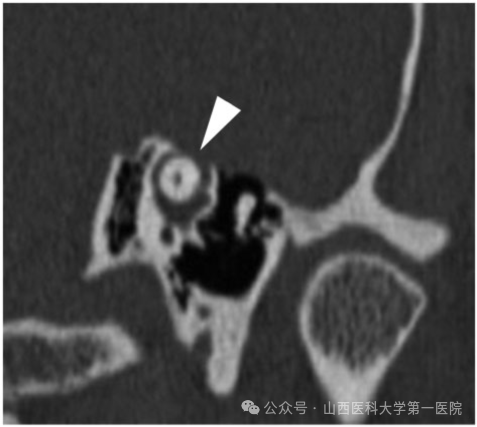

图:颞骨CT上可见上半规管出现骨质缺损

●高分辨率颞骨CT扫描:这是诊断的金标准,可以清晰地显示上半规管顶部的骨质缺损。需要特定的薄层扫描和重建技术。